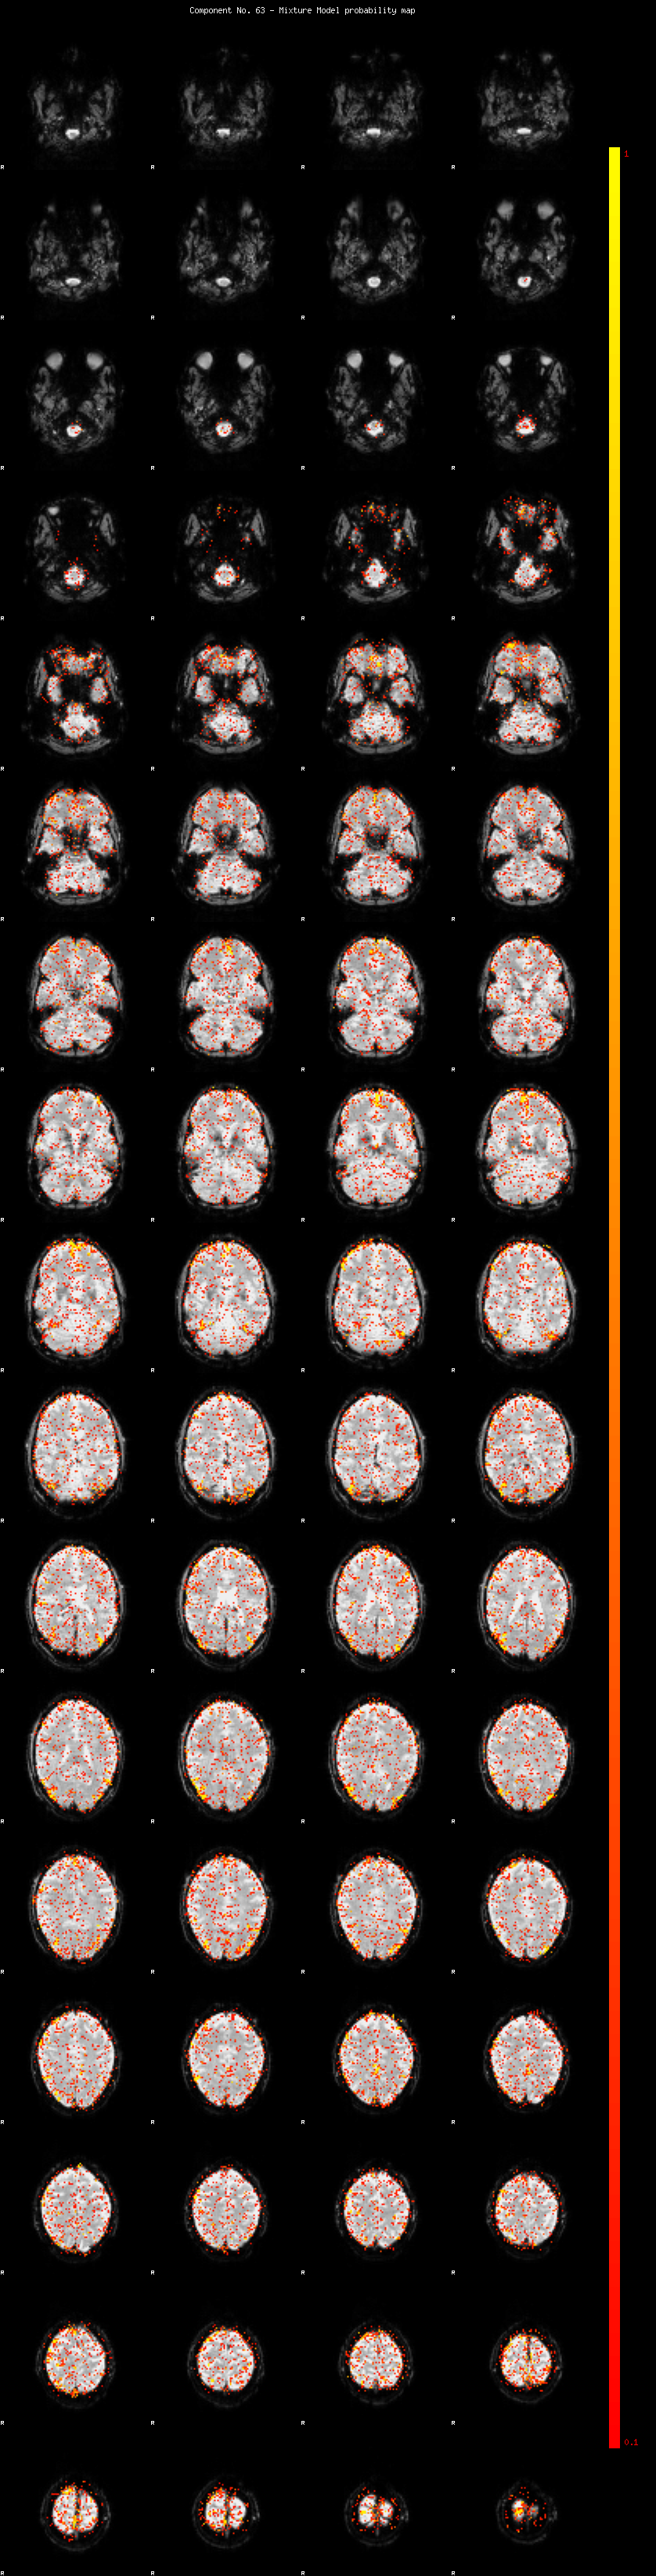

IC_63 Mixture Model fit

Means : -0.000000 2.329609 -2.384979

Vars : 1.000000 1.533915 0.715545

Prop. : 0.945492 0.039482 0.015027